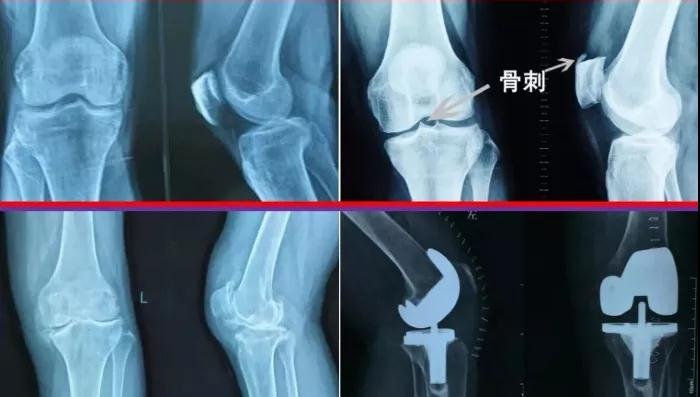

骨刺,又称骨赘、骨质增生,是在正常骨骼边缘形成的骨性增生物,常出现在受骨关节炎影响的关节周围。其常见部位包括脊柱、肩、手、髋、膝和足。

【什么样的骨刺需要治疗?】

凡事都两面性,骨刺也一样。当关节软骨遭受破坏,机体修复性地长出了“骨刺”后,其实是为了提升整体的稳定性,避免继续遭到损伤。大部分情况下,人体并不会对细小的骨刺感到有什么不适感,只有当进行影像学检查后才发现存在骨刺。

发生骨质增生后,随着关节用的次数继续增加,导致构成关节的各种组织如软骨等就会很大概率出现老化、发炎等反应,这些变化导致关节周围的组织受刺激或者受压迫,从而引起肿胀疼痛等一系列症状,如颈痛、腰痛、肢体疼痛或神经疼痛、关节疼痛等,这个时候骨刺就需要治疗了。

骨刺大多数情况下是不需要治疗的。骨刺往往会引起严重疼痛,走路不方便,但是绝大多数情况下,跟骨骨刺都不需要手术切除,只有膝关节关节面边缘及中间增生的骨刺,当骨刺引起关节软骨磨损,或者形成游离体卡主关节的时候,才需要手术治疗,通过休息,穿软底鞋,外用扶他林乳剂,口服非甾体消炎,配合外用贴剂,通常都能够缓解。